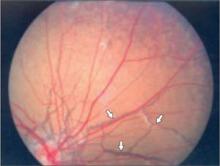

There were angioid streaks on funduscopic examination (FIGURE 2). Her lungs were clear to auscultation and percussion. Her cardiovascular exam was normal; there were no carotid bruits, and peripheral pulses were normal. The abdomen was soft and nontender; no hepatosplenomegaly or masses were present. We found no peripheral edema or cyanosis. A neurological exam was unremarkable.

FIGURE 2

Cause of the patient’s declining vision

A funduscopic exam revealed angioid streaks (arrows).

Ocular changes. Angioid streaks of the fundus are the most common ocular findings and are associated with pseudoxanthoma elasticum 85% of the time.2 They result from a rupture of the elastic tissue in the Bruch’s membrane of the retina. Angioid streaks may become less marked with time or disappear in conjunction with generalized atrophy of the retinal pigmentum epithelium.15 The visual prognosis for patients with angioid streaks is often poor.

Other retinal changes include macular degeneration, altered pigmentation (eg, peau d’orange appearance), subretinal neovascularization, and chorioretinal scarring. Ocular hemorrhage can occur even with minimal trauma. Hu et al described one fundus feature that seems to be typical of pseudoxanthoma elasticum: comet-like tails.1